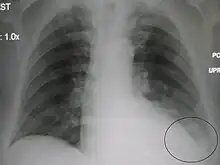

| A parapneumonic effusion (circled), due to a left lower lobe pneumonia. |